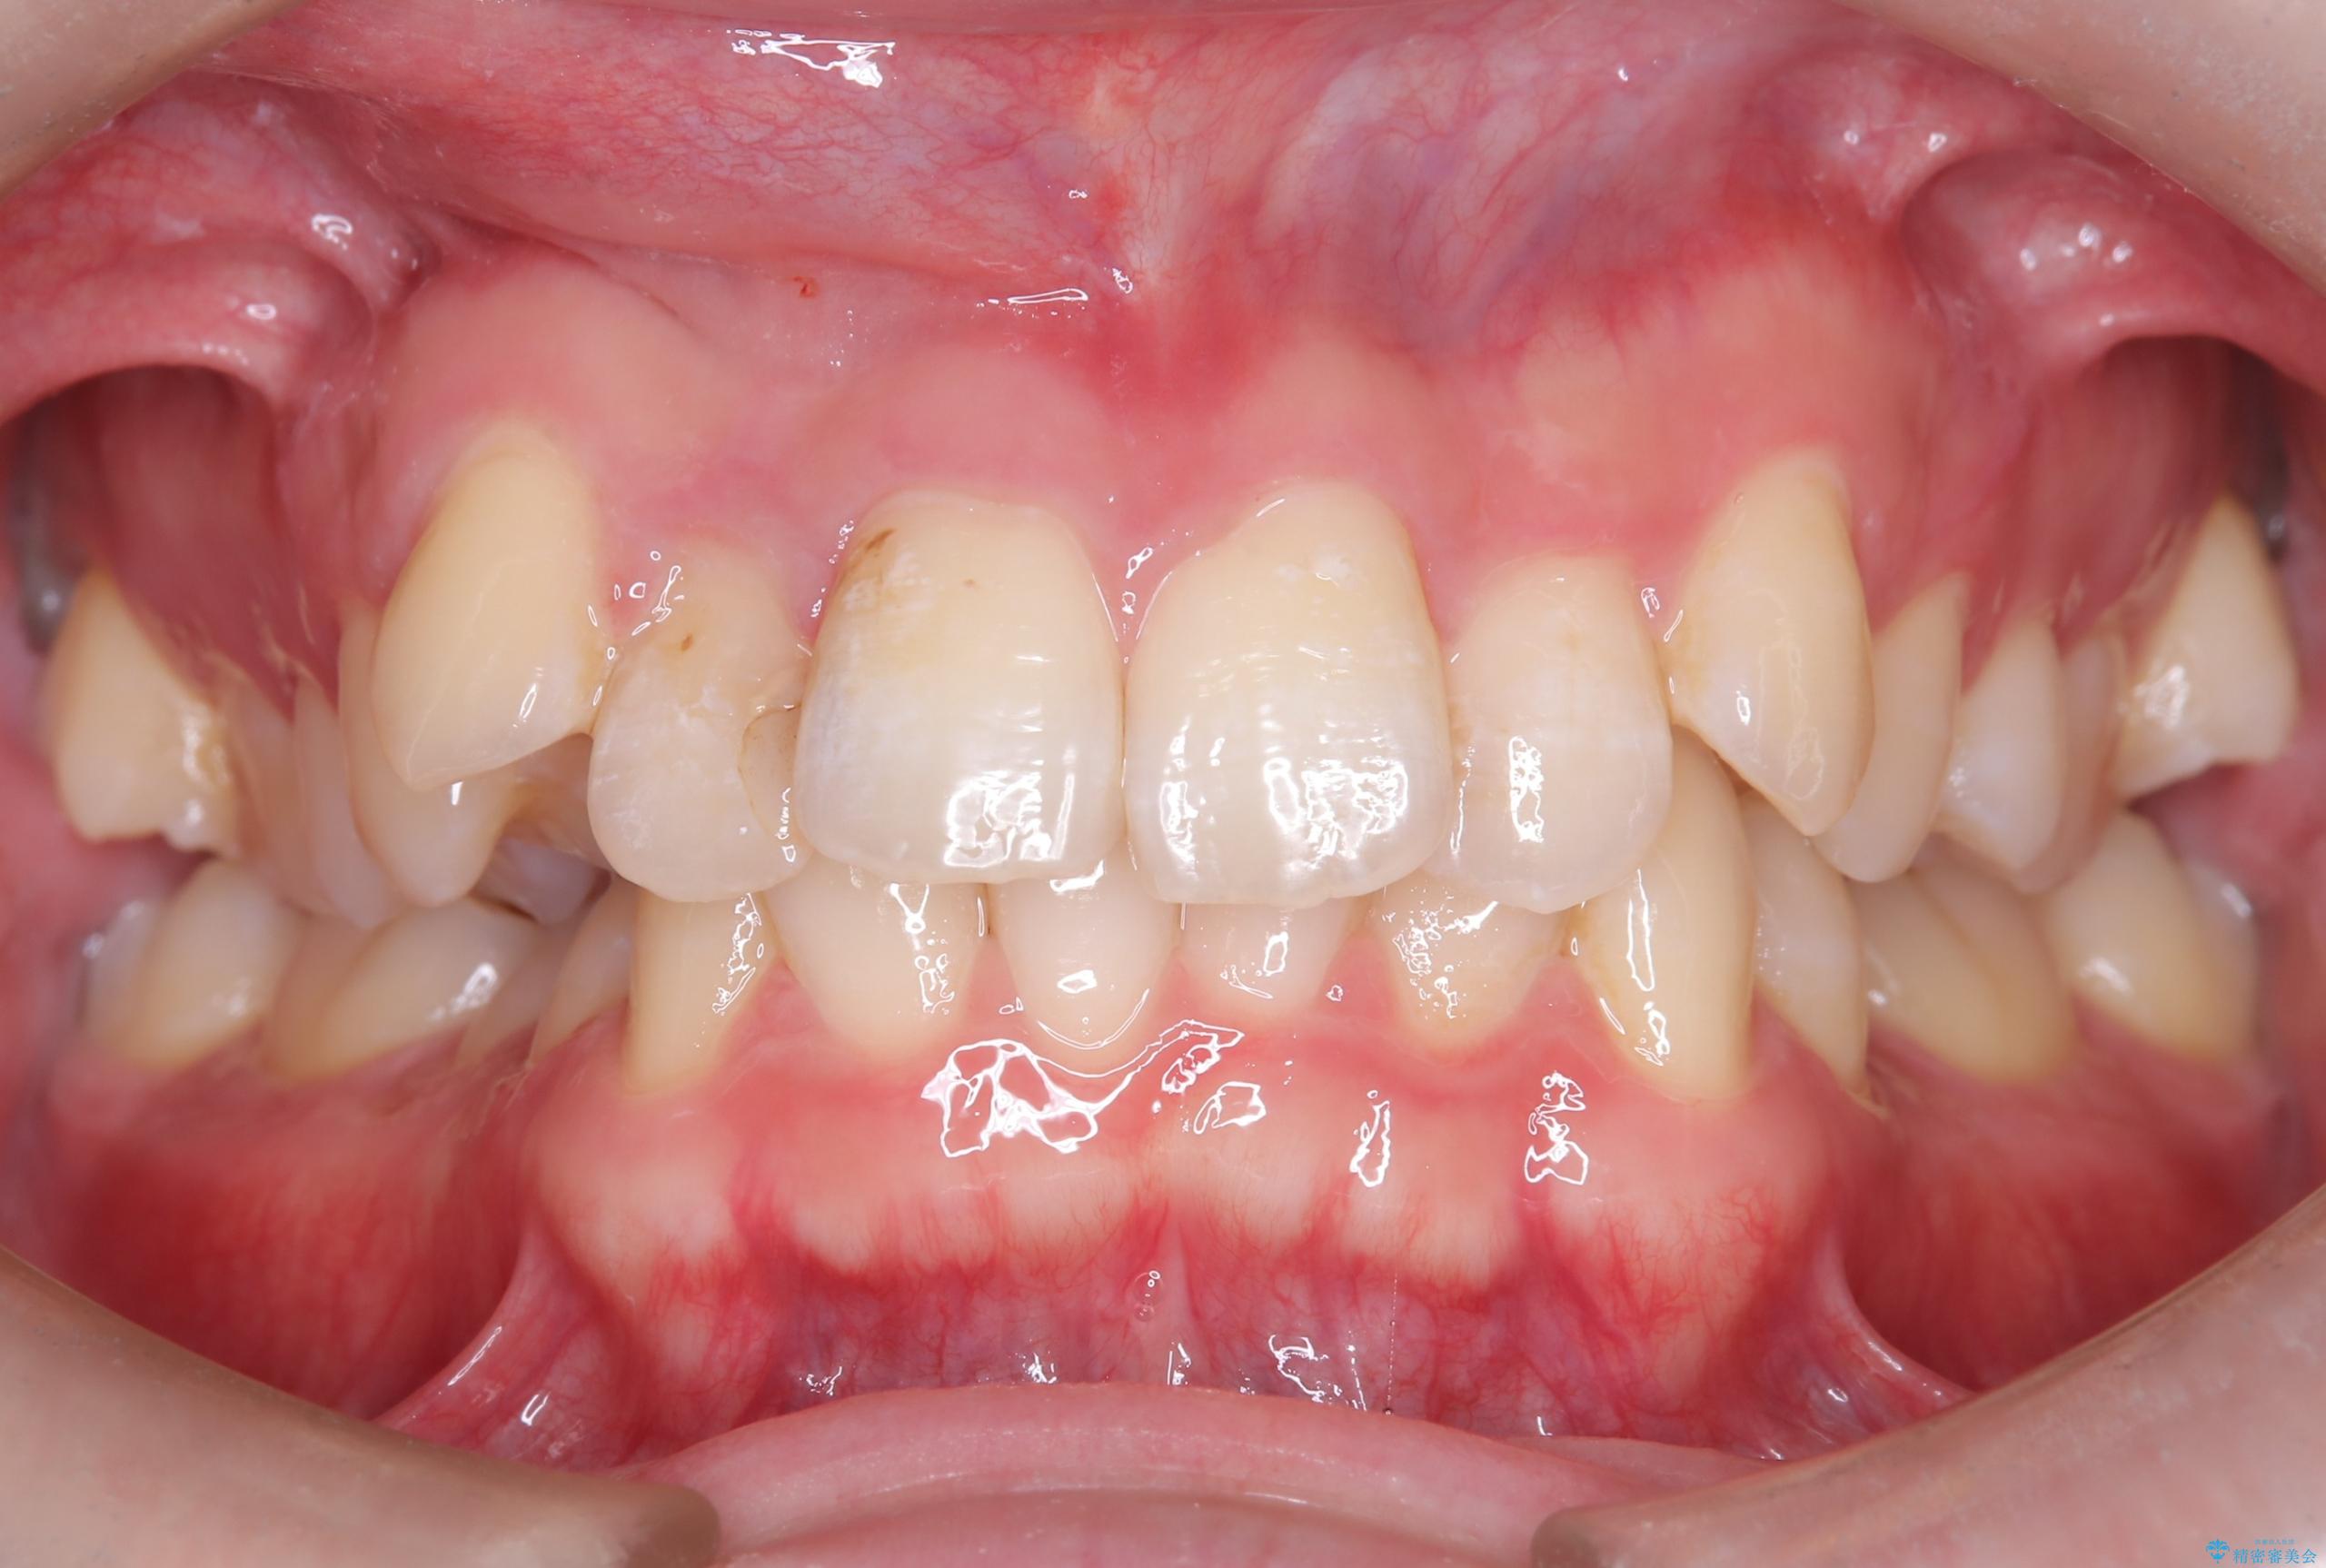

- 主訴:右上の前歯が何しなくても痛い

右上2番の歯に自発痛を認め、症状や歯髄診・レントゲン像から不可逆性歯髄炎と診断し、精密根管治療から歯冠補綴まで行うこととなりました。

初診時に歯髄診断を行い、不可逆性歯髄炎と診断し抜髄から補綴修復までの流れを説明し、精密根管治療、ファイバ-コア築造、オールセラミッククラウン(St)修復を行うこととしました。